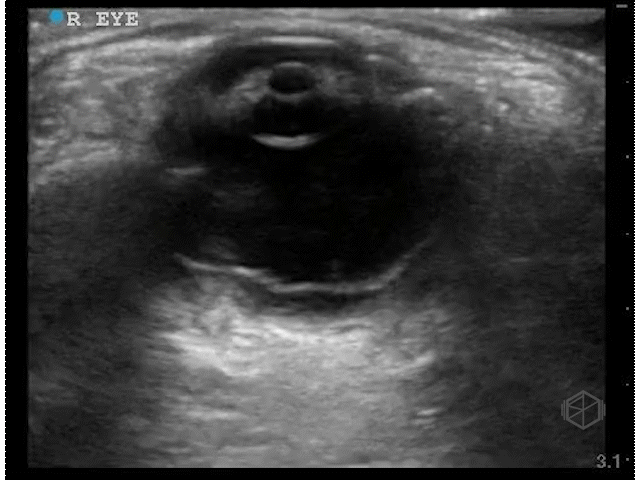

Dr. Singh scanned a ~40-year-old male with a past medical history of diabetes, hypertension, and substance abuse with diminished vision for 3 weeks.

These clips are good — there is a scan both ways through the eyes in transverse and sagittal orientations. There appears to be something irregular the posterior aspect of the vitreous, however there is not enough detail.

Dr. Singh appropriately did the next step — he increased the gain significantly and performed oculo-kinetics (have the patient move their eye rapidly).

The above clips demonstrate some interesting pathology. There appears to be a hyperechoic flap tethered to the optic nerve. This patient has a retinal detachment. There may also potentially be a vitreous detachment.

• Retinal detachment appears as a thick hyperechoic membrane. It can be tethered to the optic nerve if large, or if smaller (or not close to to the optic nerve), attached to another portion of the posterior wall of the eye. The retinal detachment will move slightly with oculo-kinetics but will remained tethered. POCUS has a high sensitivity and specificity if done correctly for the detection of retinal detachments.